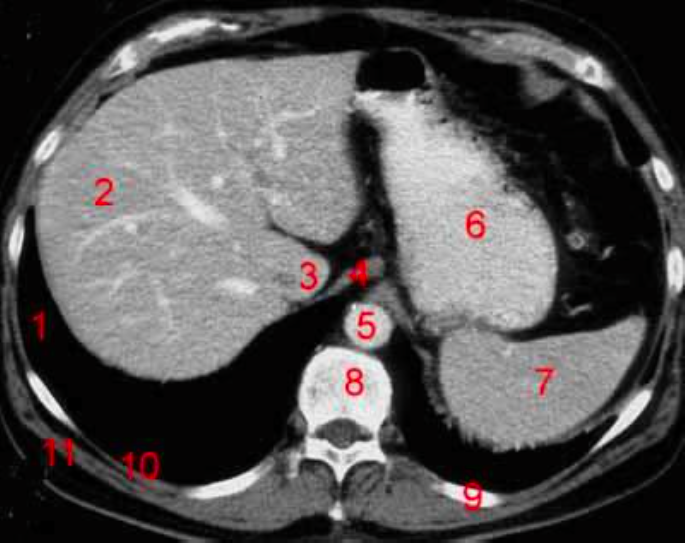

Number 1?

R kidney

Number 2?

Rt lobe of liver

Number 4?

Head of pancreas

Rt diaghragmatic crus

IVC

Rt lobe liver

R lung

Number 10?

Rt rib